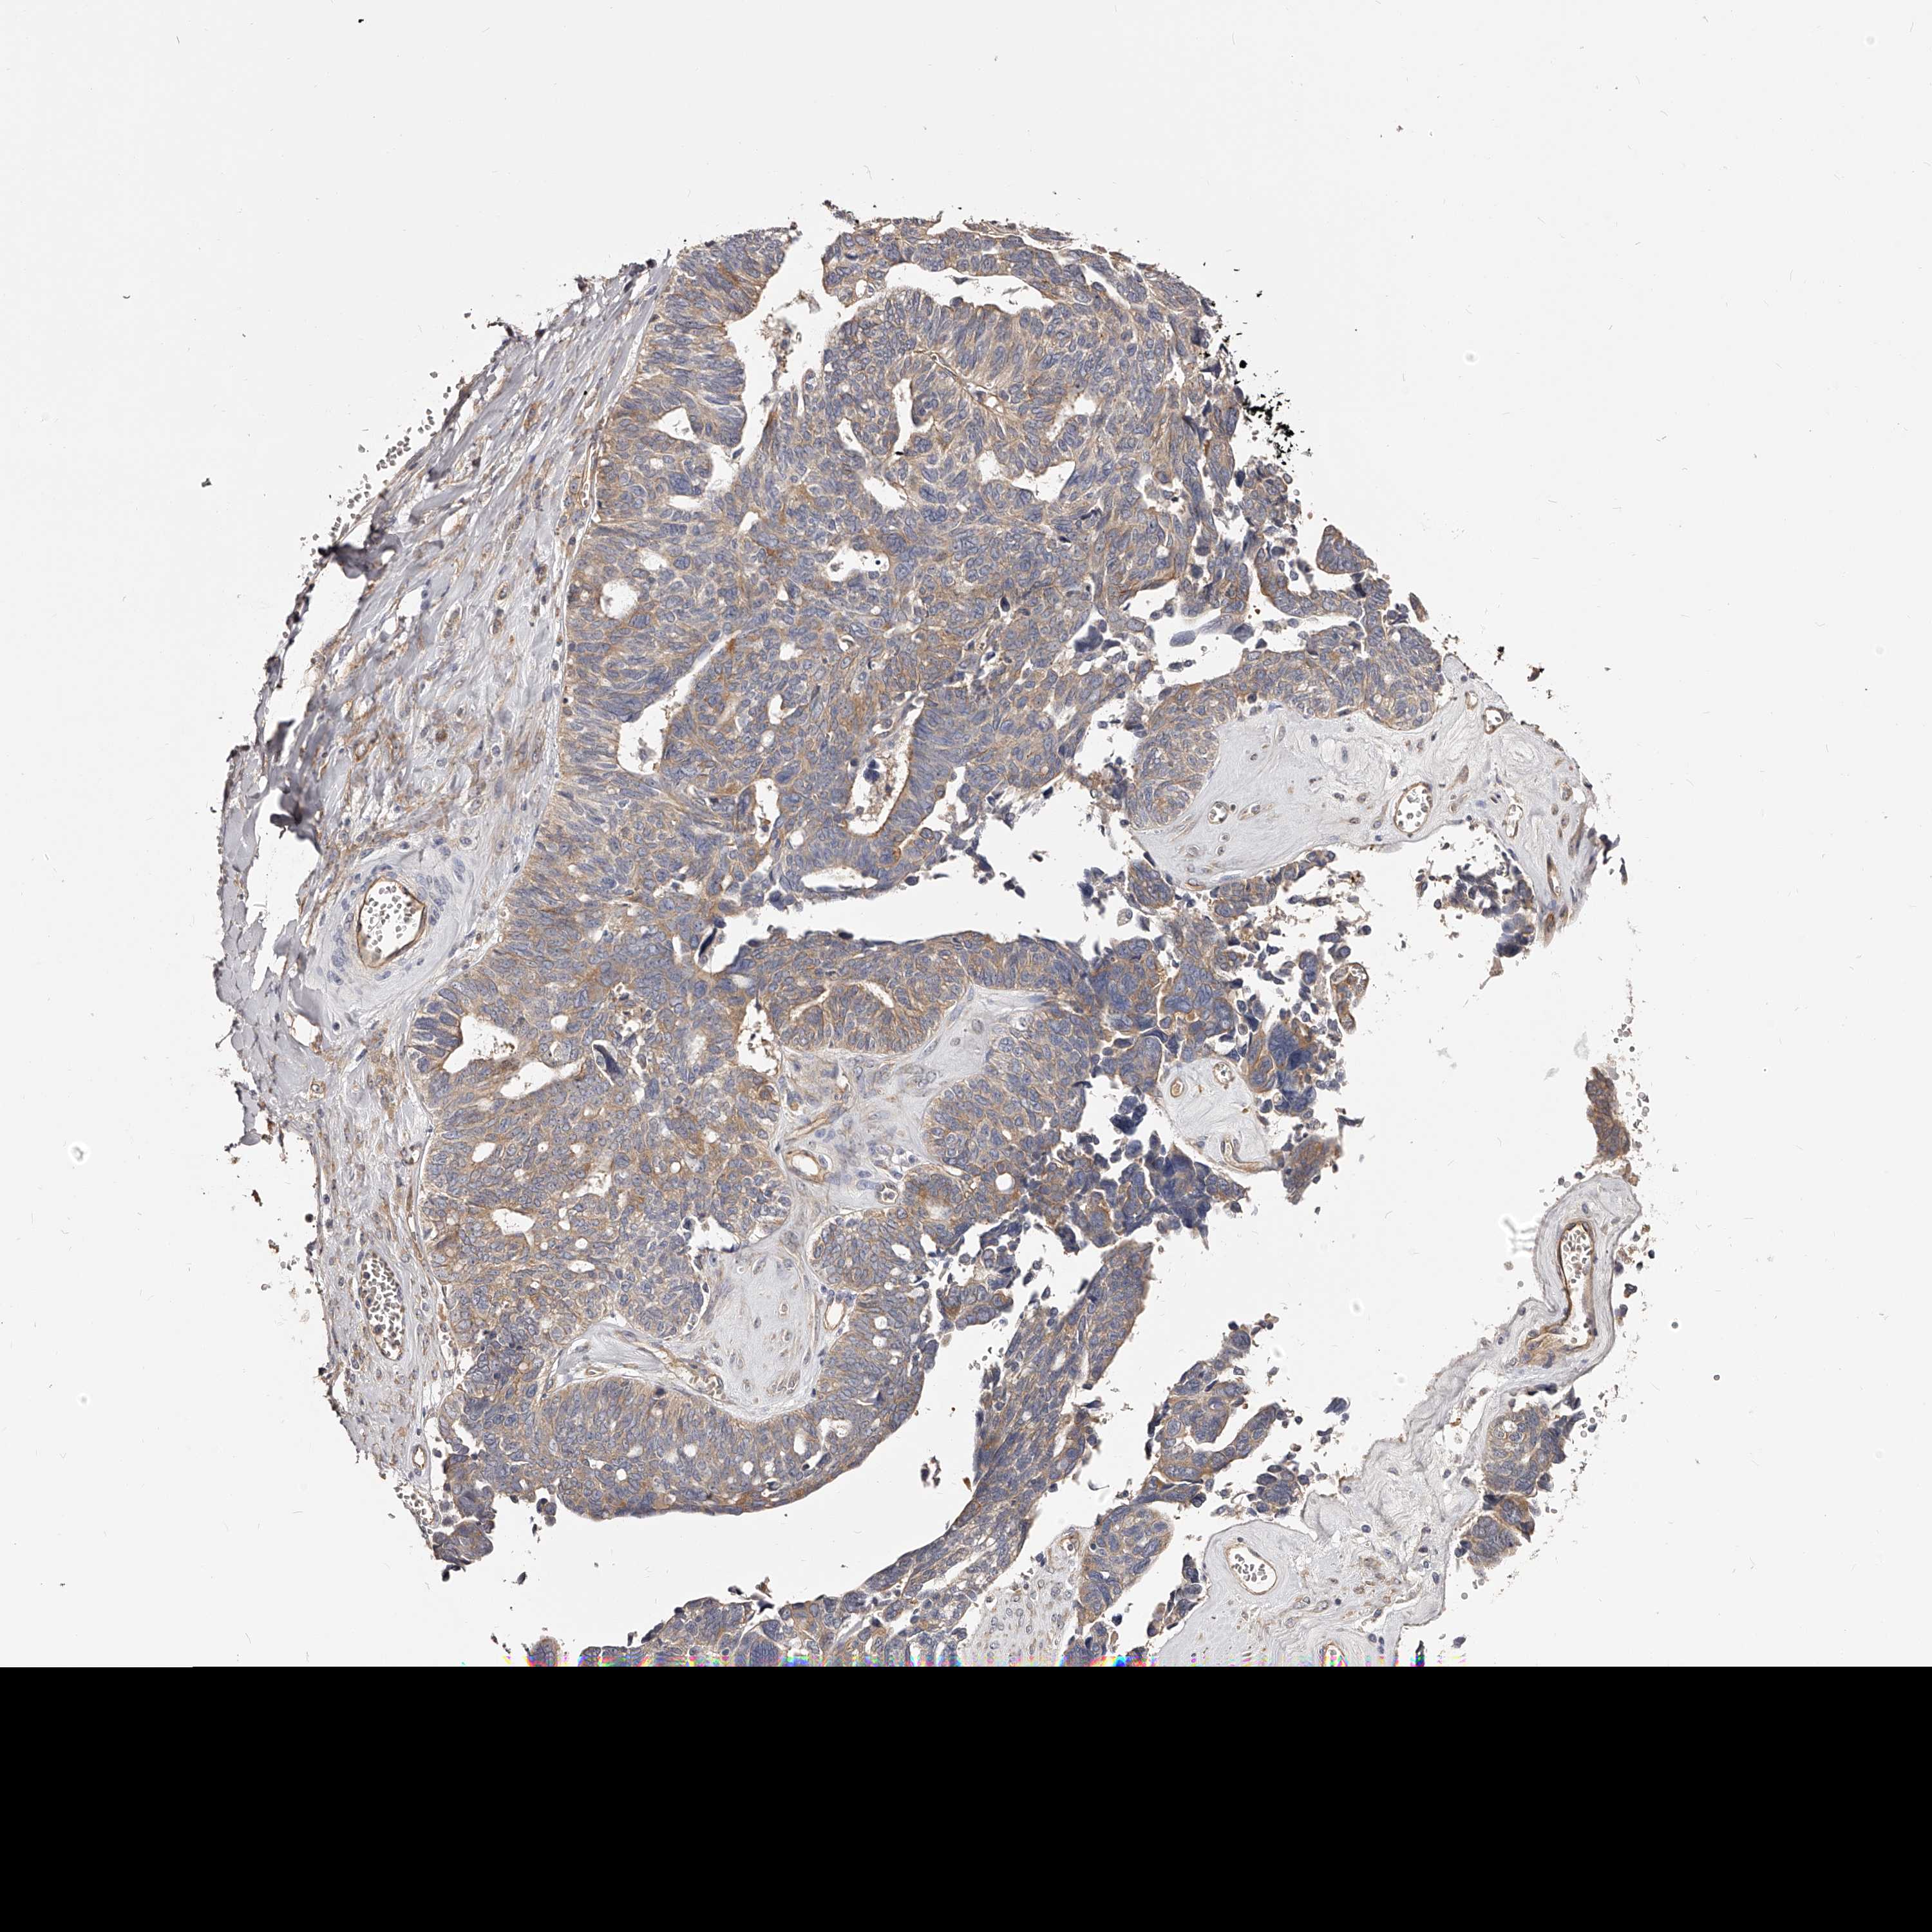

OVARIAN CANCER - Protein expressioni

A mouse-over function shows sample information and annotation data. Click on an image to view it in a full screen mode. Samples can be filtered based on level of antibody staining by selecting one or several of the following categories: high, medium, low and not detected. The assay and annotation is described here.

Note that samples used for immunohistochemistry by the Human Protein Atlas do not correspond to samples in the TCGA dataset.

Antibody stainingi

Antibody staining in the annotated cell types in the current human tissue is reported as not detected, low, medium, or high, based on conventional immunohistochemistry profiling in selected tissues. This score is based on the combination of the staining intensity and fraction of stained cells.

Each image is clickable and will lead to virtual microscopy that enables deeper exploration of all samples and also displays staining intensity scores, fraction scores and subcellular localization as well as patient and tissue information for each sample.

Antibody HPA030159

Antibody HPA030160

Antibody HPA030161

Cystadenocarcinoma, serous, NOS